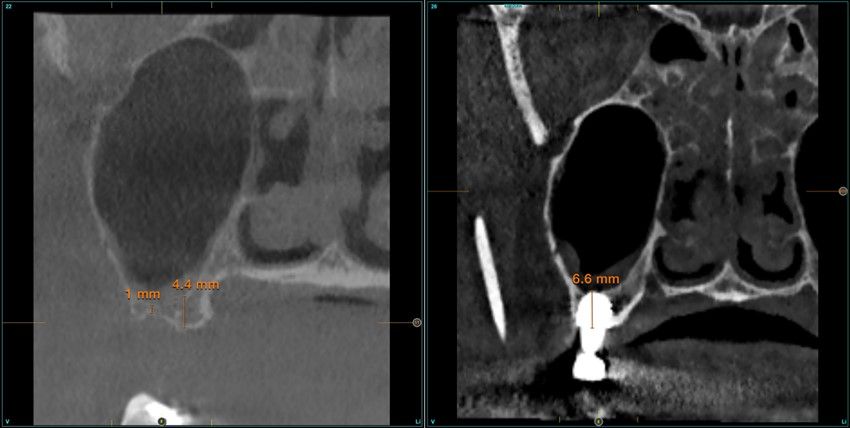

Resultados. Fueron reclutados 13 pacientes en los que se insertaron 30 implantes. Una vez insertados y cargados los implantes, la altura media final fue de 9,68 mm (+/- 2,66), lo que supone una ganancia promedio de 5 mm. A los 10 años, se observó una disminución media de la altura ósea ganada en los implantes en conjunto de 0, 29 mm (+/- 0,77). La media de la pérdida ósea mesial fue de 0,73 mm (+/- 0,75 mm) y la media de la pérdida ósea distal fue de 0,98 mm (+/- 1,2 mm). La supervivencia fue del 100%.

Results.Thirteen patients were recruited and 30 implants were inserted. Once the implants were inserted and loaded, the mean final height was 9.68 mm (+/- 2.66), which represents an average gain of 5 mm. At 10 years, there was a mean decrease in the overall bone height gain of the implants of 0.29 mm (+/- 0.77). The mean mesial bone loss was 0.73 mm (+/- 0.75 mm) and the mean distal bone loss was 0.98 mm (+/- 1.2 mm). Survival was 100%.

Los senos tratados con la técnica de elevación transcrestal sin material de relleno muestran un incremento de entre 2,5 mm12,13 hasta 4.4 mm14,15 en la altura ósea lograda sobre el ápice y una supervivencia de los implantes que se sitúa entre un 94 y un 100%16-17. En este trabajo se presenta un estudio retrospectivo donde se ha evaluado la inserción de implantes extracortos (5,5 y 6,5 mm) en zonas posteriores maxilares mediante la técnica de elevación de seno transcrestal con la fresa de ataque frontal sin la utilización de material de injerto, con un tiempo de seguimiento de 10 años para poder objetivar el comportamiento de los implantes a largo plazo y de la técnica empleada.